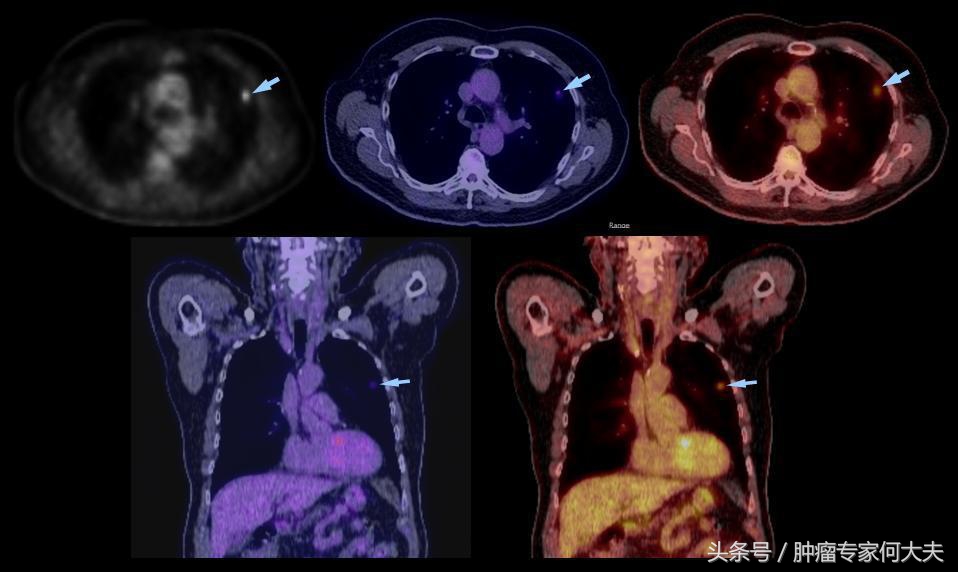

在第二年接近第三年的那次复查中,小豆被医生告知右肺也长了瘤子,医生建议小豆穿刺活检,小豆还是比较配合的,做了肺穿刺活检术,术后病理结果证实也是肺腺癌,和以前病理结果一样,医生推测可能是转移,并对取下的组织进行了基因检测,仍然没有检测到敏感突变基因,但医生建议小豆可以尝试口服“易瑞沙”,因为在生病的2年多时间里,小豆研读了很多肺癌的专业书籍,对肺癌的知识了解甚多,因此她同意了口服靶向药,在口服靶向药的两个月里,除过面部皮疹,没有其他不良反应,但用药三个月后,复查肺部CT,病灶依然没有明显变小迹象。医生考虑无效,于是就把靶向药停了。没有任何治疗,她还能撑多久?她自己不知道,医生们也众说纷纭,反正总体是时间不会太久,有的医生说也就半年一年左右,小豆说当时自己想“反正都这样了,与天争命也无济于事,静静等待未来会发生什么”。

就这样,读书、看报、上网,有时候和朋友出去游游逛逛,虽然癌症在身,她不能积极作为,只能听天由命,但是半年过去了,右肺出现的病灶生长势头不明显,一年过去了,两年过去了,三年过去了,一直在复查,但是复查的结果总是说变化不显著。但医生仔细对比三年之初与三年之末(最近)的片子,瘤子是有所长大,但都长的不算多,个别小病灶甚至自然变小。 最近,小豆说自己喘的明显了,夜里咳嗽厉害,难以成眠,要来查查,我给做了胸部CT检查,结果提示两肺多发占位病变,对比了她3年前刚发现右肺时的片子,这次明显变大,目前尚未做出诊疗计划。但对于小豆这样的病人,实属少见。人类对于肿瘤的认识仍然处于很原始的阶段。就拿肺癌来说,现代医学研究算是比较成功的一种瘤种,已经认识到一部分肺癌患者因为存在某些基因突变可以从治疗中获益,但是没有突变的患者并不是一定就很危险,个体差异相当大。希望每个人不要因为得了肿瘤,就自暴自弃。